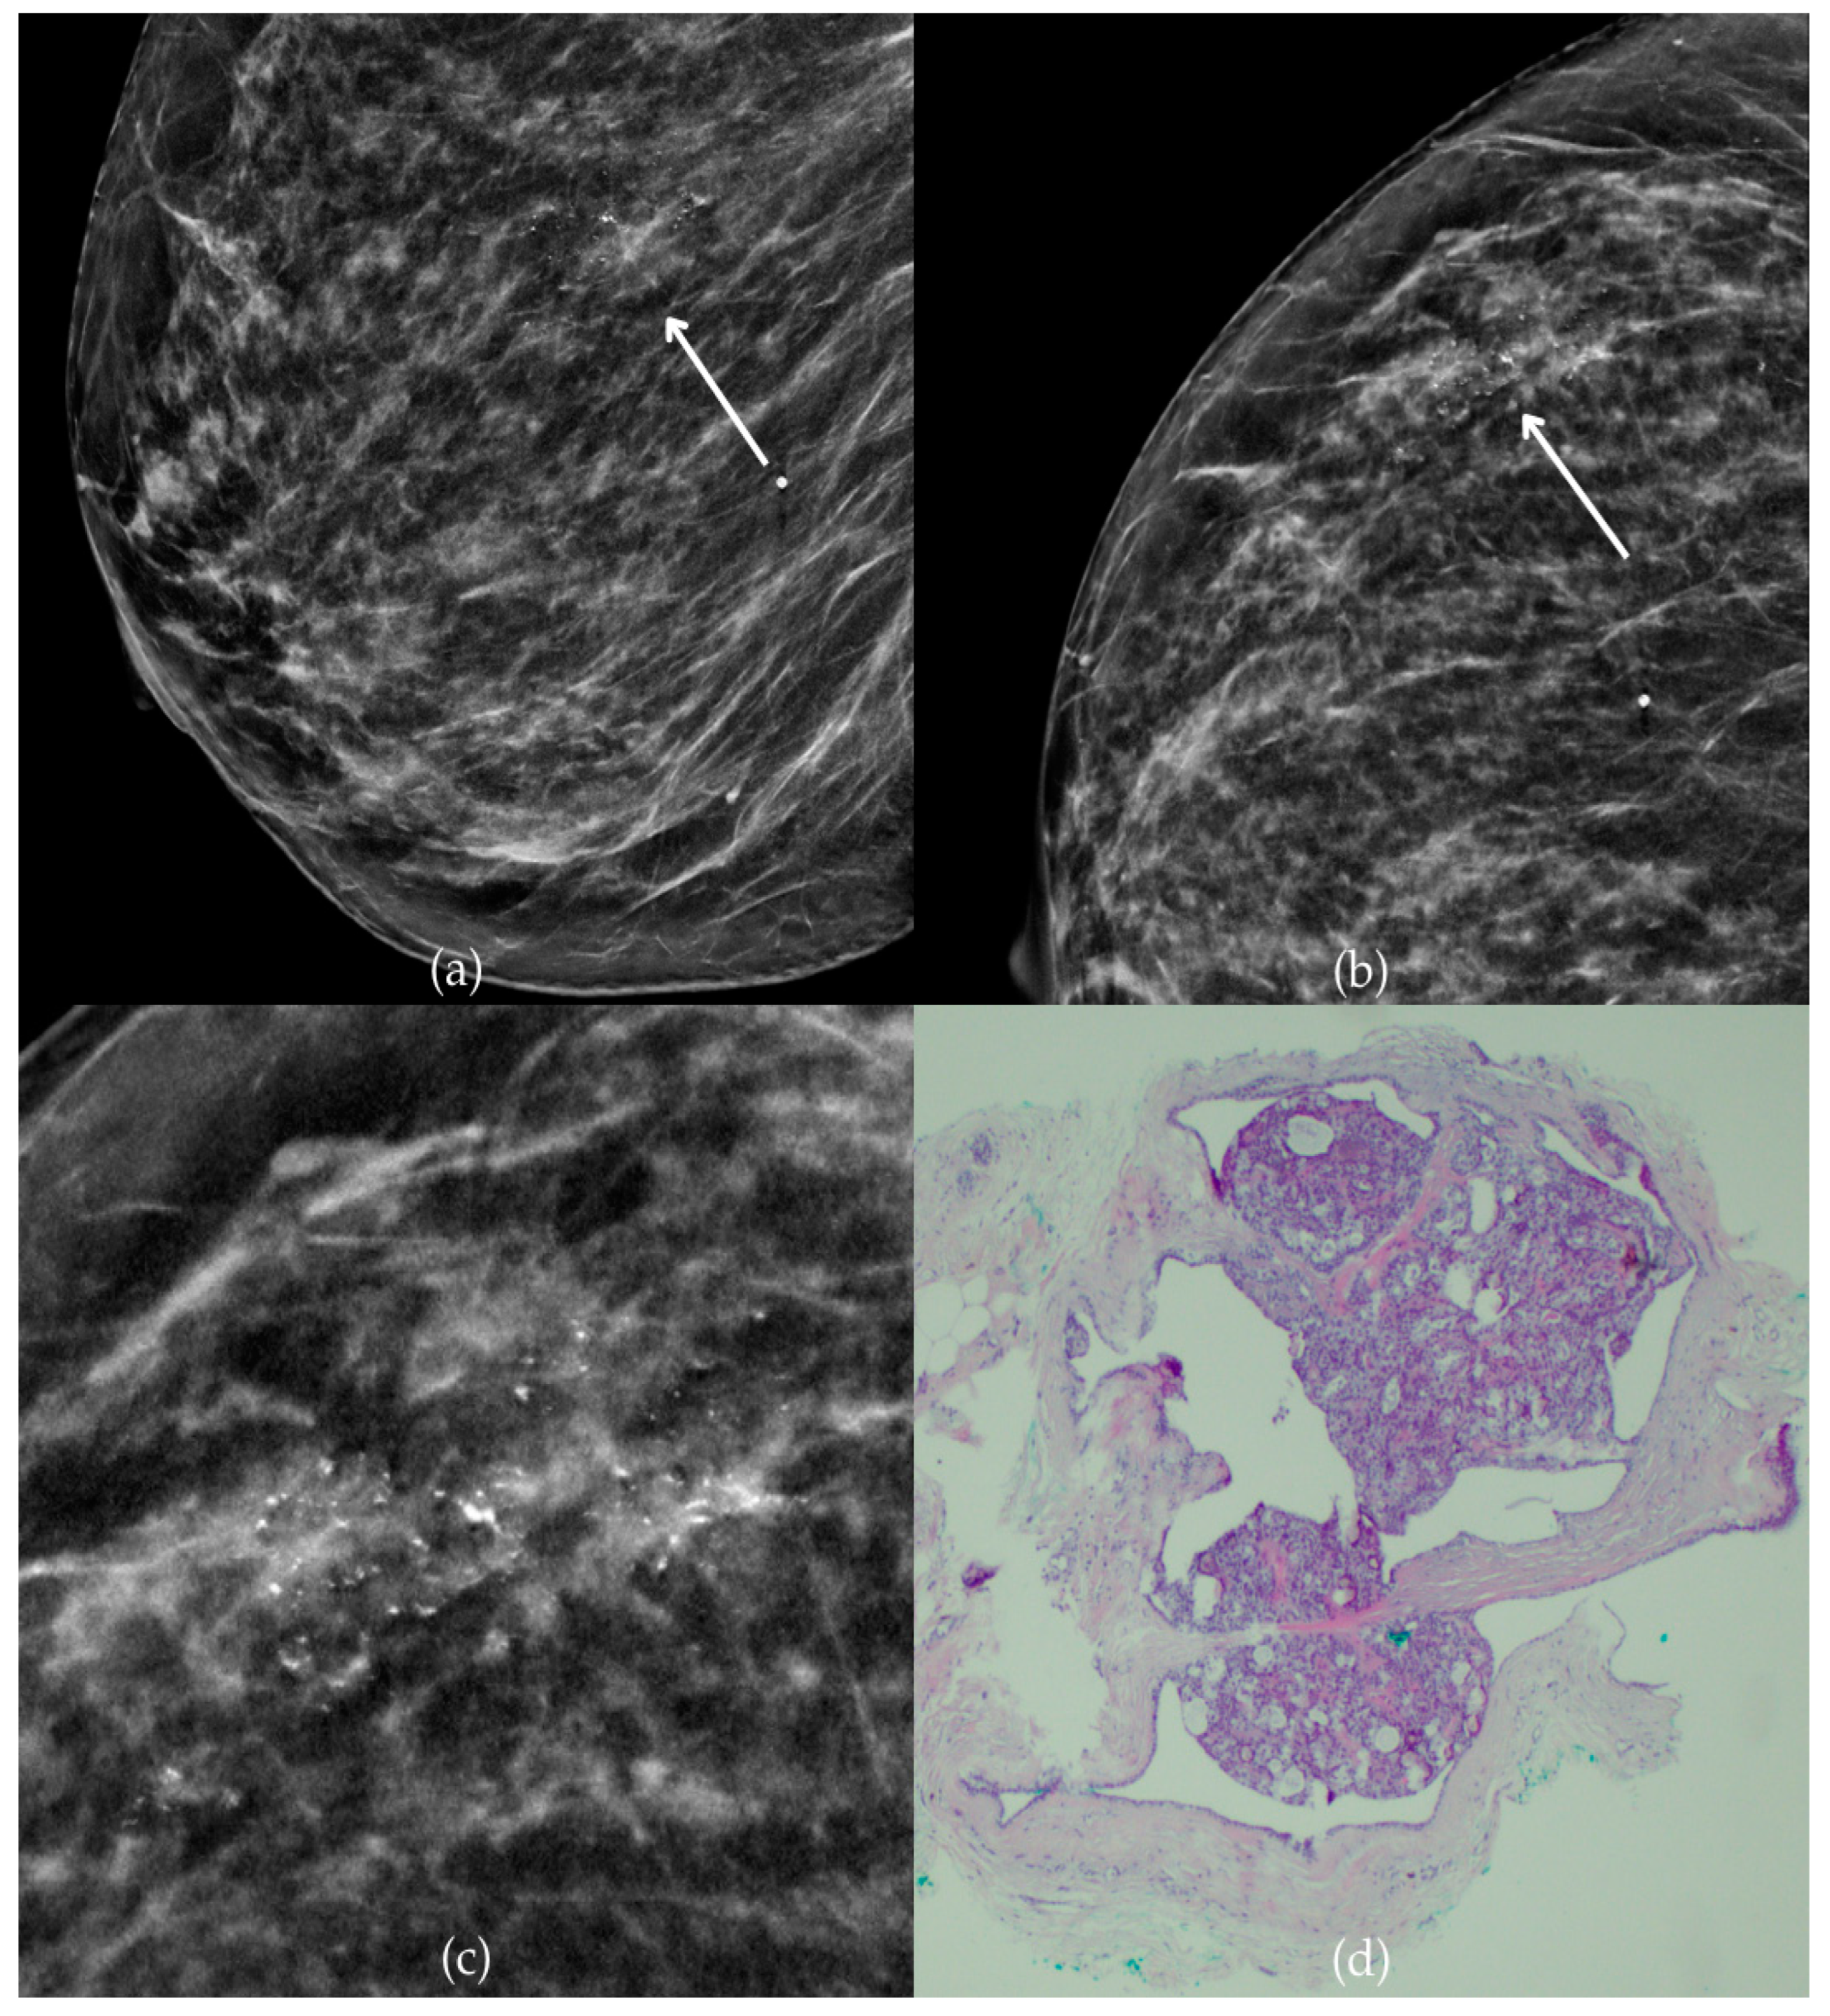

During a screening program, a 64-year-old patient presented with suspicious microcalcifications. The mammogram shown in Figure 3 of the patient’s right breast revealed a segmental distribution of coarse heterogeneous and fine pleomorphic calcifications in the upper outer quadrant, corresponding to a BI-RADS 4 finding. Tissue analysis obtained through VABB confirmed the presence of invasive carcinoma (category B5b). The patient underwent a mastectomy. Postoperative pathology showed only an in situ component, with no evidence of an invasive component, indicating that the invasive component was removed during the biopsy. One year after diagnosis, the follow-up US was reported as BI-RADS 2 classification, indicating benign imaging features.

Figure 3.

Invasive breast cancer. (a) Mediolateral oblique (MLO) mammography view; (b) craniocaudal (CC) mammography view of the right breast showing coarse heterogeneous and fine pleomorphic calcifications (marked with arrows) in the upper outer quadrant, with segmental distribution. (c) Magnified mammographic image of coarse heterogeneous and fine pleomorphic calcifications with segmental distribution. (d) The histopathological image of the biopsy sample shows the characteristic features of invasive cancer (marked with arrow) and ductal carcinoma in situ (DCIS) (marked with arrowhead) (HE staining; 40× magnification).